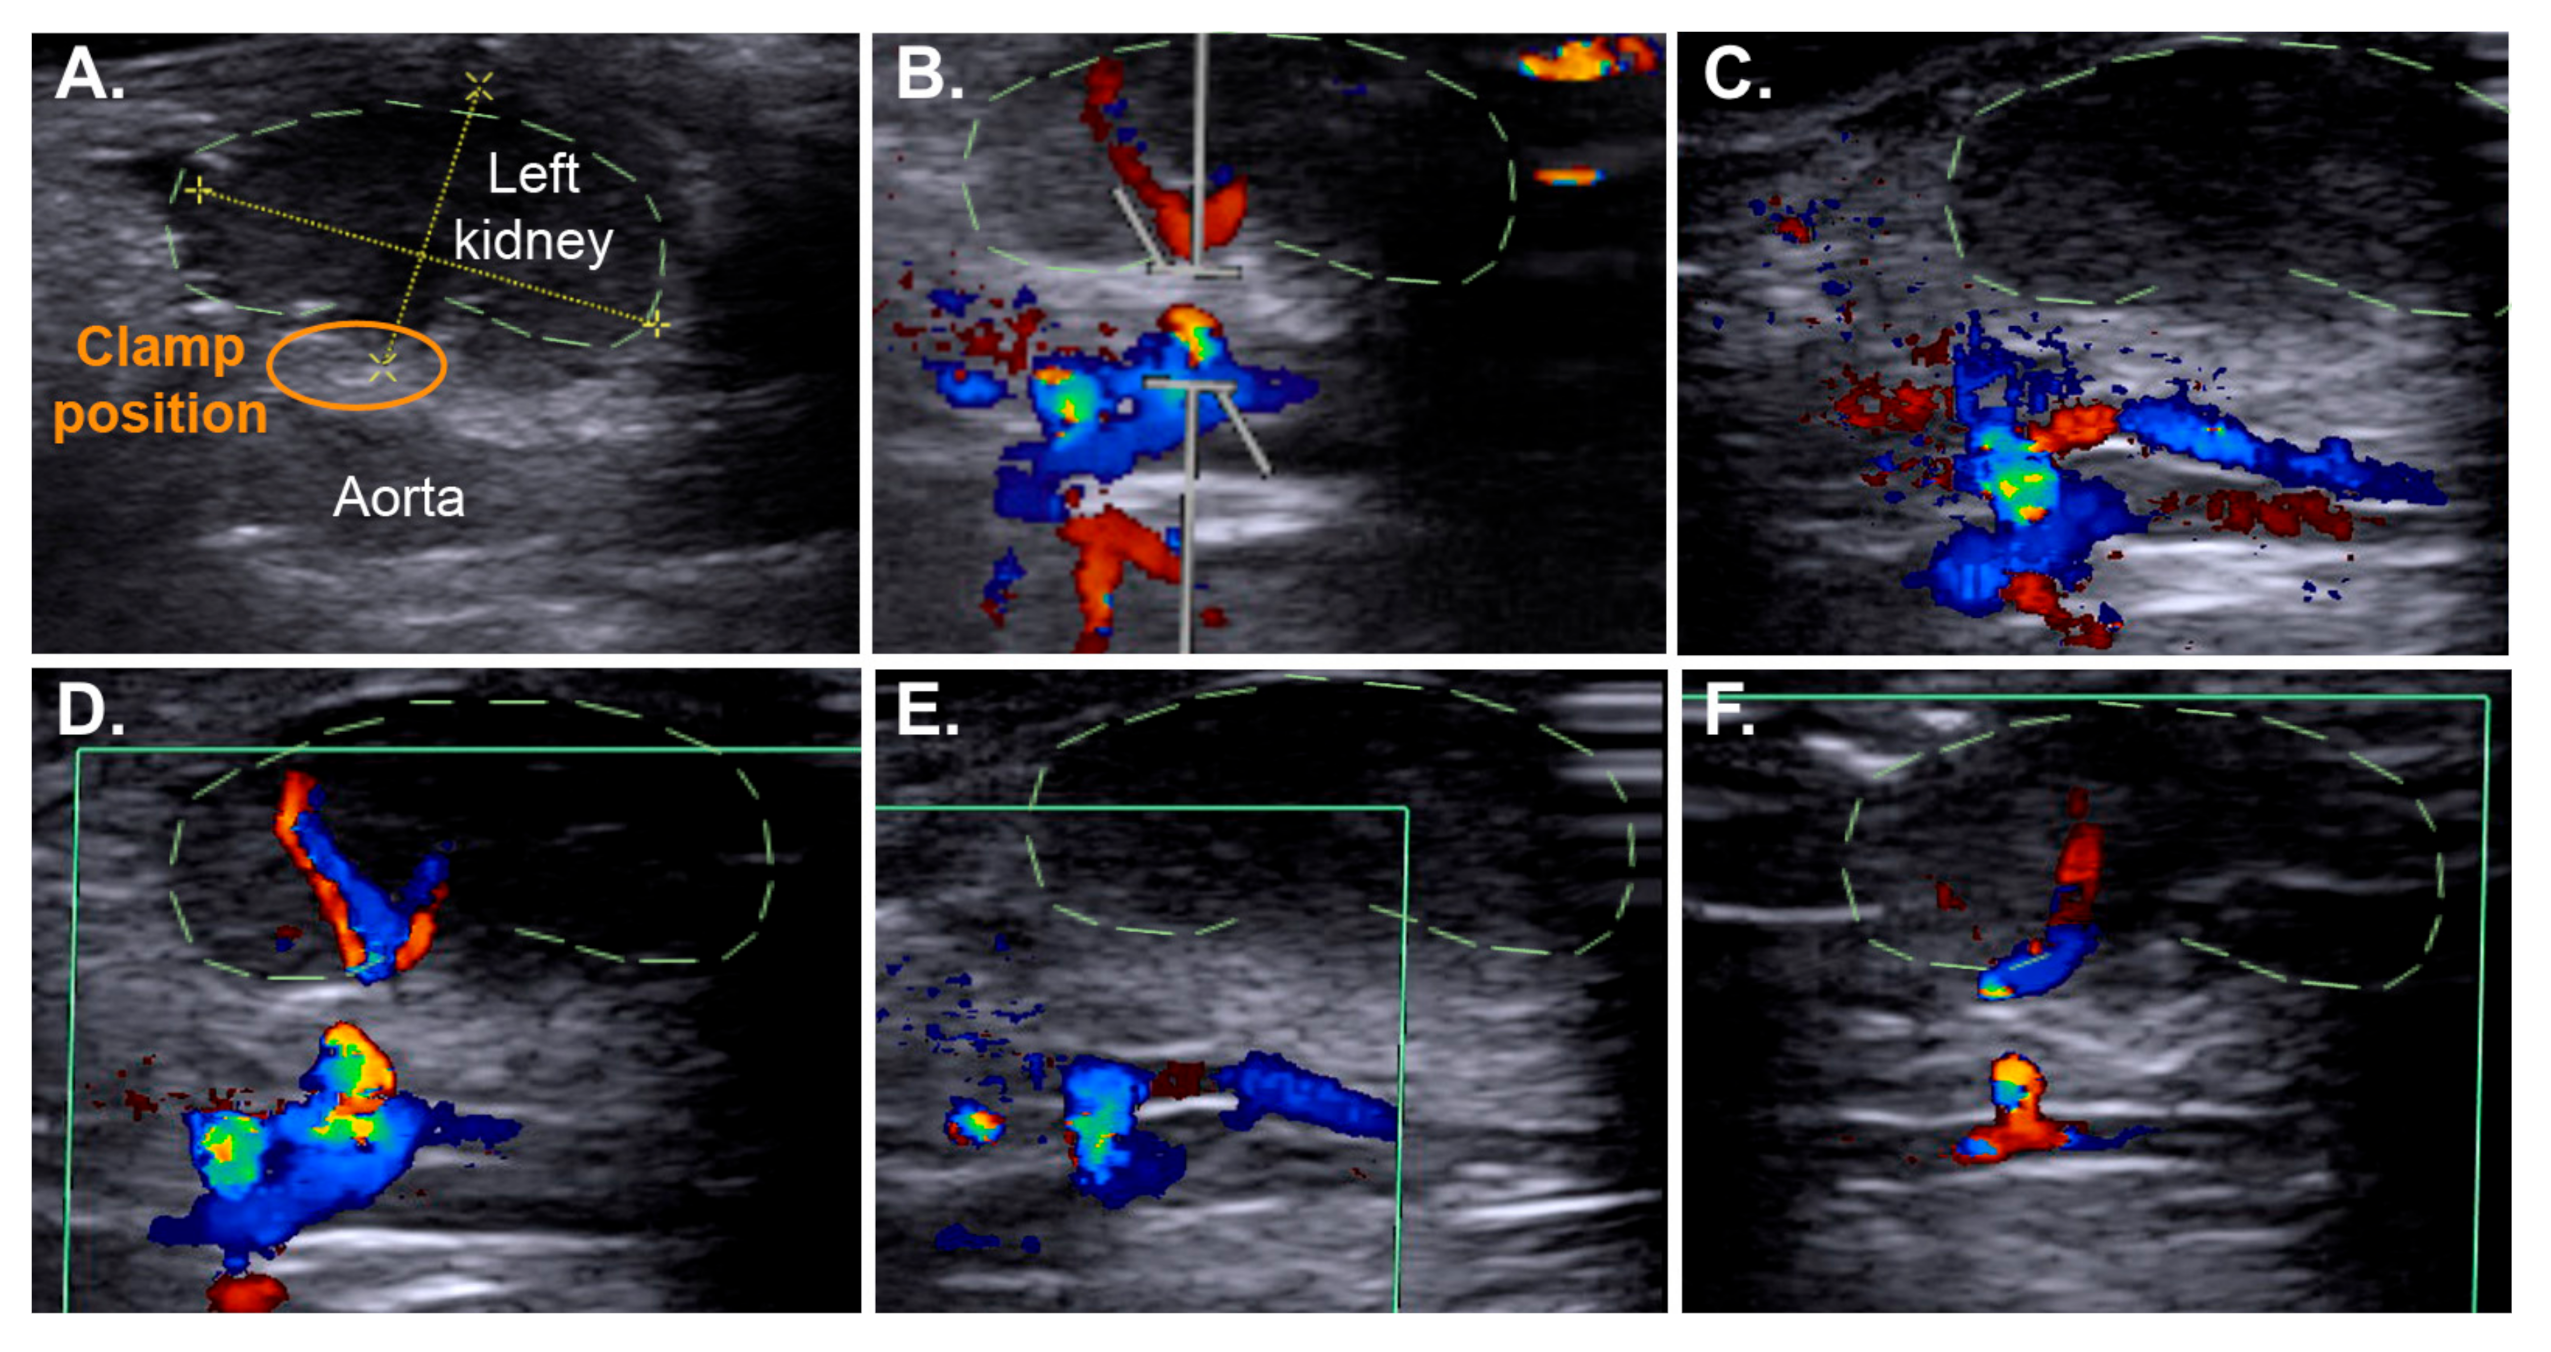

2.3. Efficient IRI Using the RIRI Clamp

4.6. Non-Invasive Ultrasound Assessment of Renal Hemodynamic